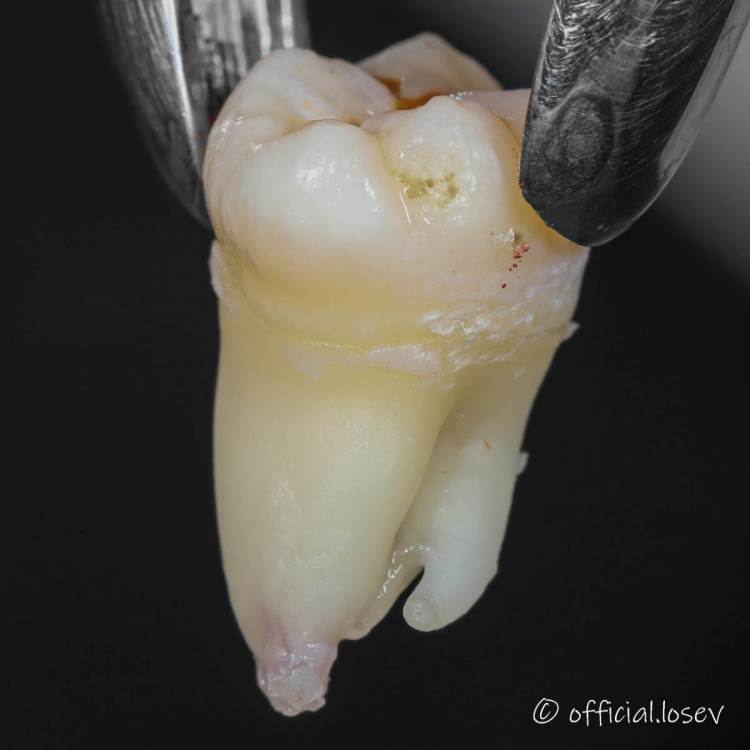

It'sGeorgy Опубликовано 12 марта, 2021 Поделиться Опубликовано 12 марта, 2021 Сегодня был Кинг-сайз: 4 Ссылка на комментарий

Raystom Опубликовано 12 марта, 2021 Поделиться Опубликовано 12 марта, 2021 Сегодня был Кинг-сайз:77ACA2FA-C768-41BD-A47A-7FB9E5267020.pngCBA9ECB9-7FF0-400F-9532-0BD5DA33C825.jpeg78D8DF61-36CB-4F3C-BD57-D07106E56D33.jpegПочти как корона из бургер-кинга) Ссылка на комментарий

It'sGeorgy Опубликовано 12 марта, 2021 Поделиться Опубликовано 12 марта, 2021 Красавцы все. И зуб и доктор!Благодарю как без распилов такой достали? Если честно, сам не понял. Был под впечатлением от ОАС на вч размером с палец, которое получил, когда верхнего удалял. Убрал кость до уровня коронки. Вестибулярно в щель байонетный элеватор и зуб вышел. Ссылка на комментарий